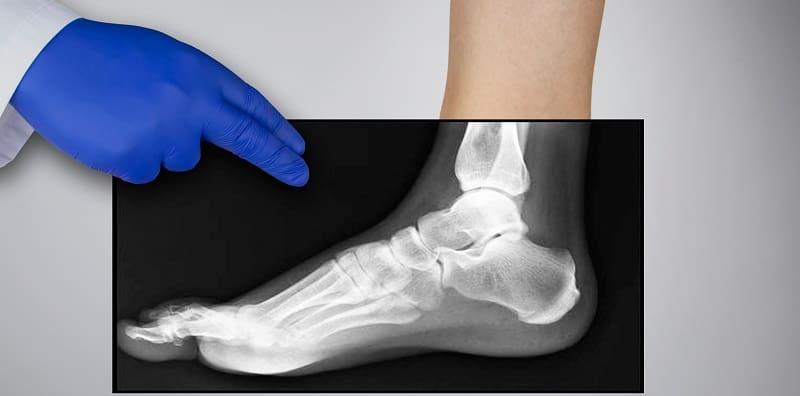

Osteoporosis bermaksud tulang yang berliang (porous). Masalah tulang ini menyebabkan pesakit kehilangan kalsium dan mineral penting daripada tulang. Akibatnya, tulang akan menjadi lebih lemah dan mudah retak.

Oleh sebab itu, penghidap osteoporosis berhadapan dengan bahaya tulang retak setiap hari. Sukar untuk mereka melakukan aktiviti harian seperti berkebun, mengangkat barang dan sebagainya tanpa menghadapi risiko kecederaan.

Masalah tulang patah dan retak merupakan keadaan yang lazim dalam kalangan pesakit osteoporosis.

Selalunya, pesakit osteoporosis akan patah tulang pergelangan tangan, tulang belakang atau tulang pinggul. Keretakan tulang pula paling banyak berlaku pada kawasan tulang belakang.

Setiap tahun, hampir 550,000 kes retak tulang belakang dicatatkan di Amerika Syarikat disebabkan penyakit osteoporosis. Ini sudah cukup untuk membuktikan betapa seriusnya penyakit ini.